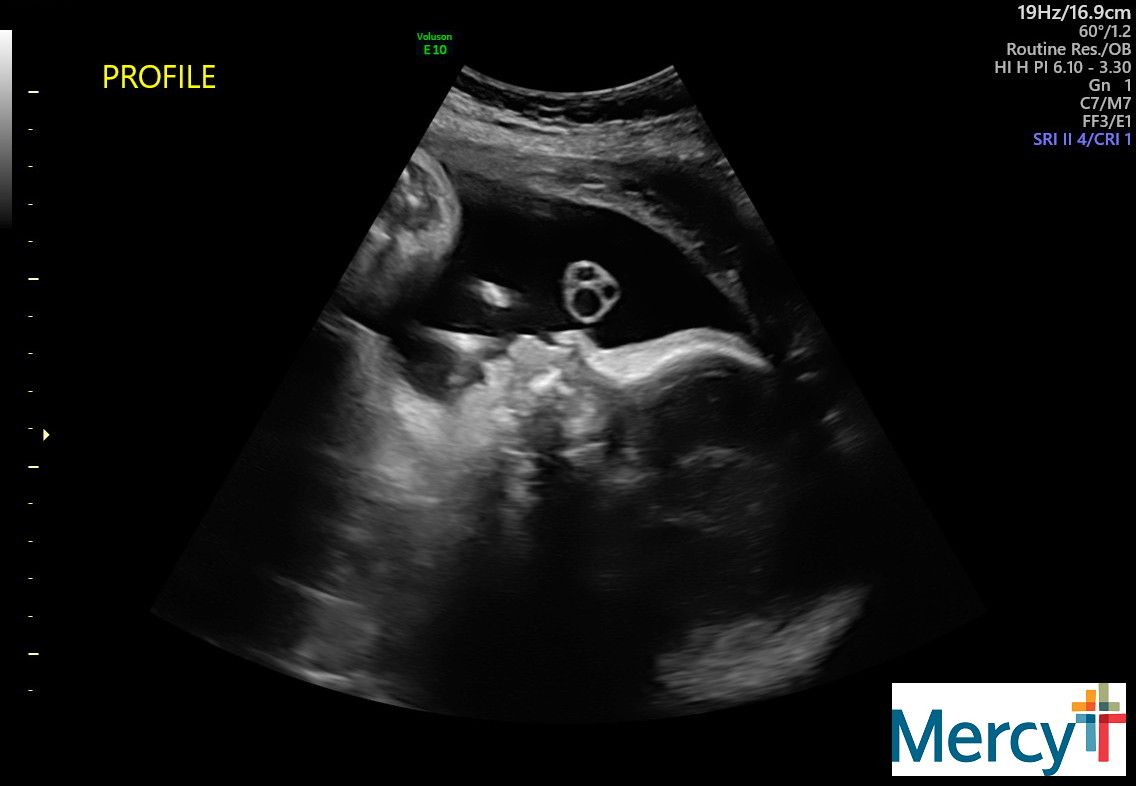

At 32 weeks my appointments would change from once a week to twice a week. These appointments would have a NST (non-stress test) and an ultrasound to check my anniotic fluid levels.

Lupus pregnancies are so complex. The placenta ages rapidly near the end and risk for stillbirth is so high.